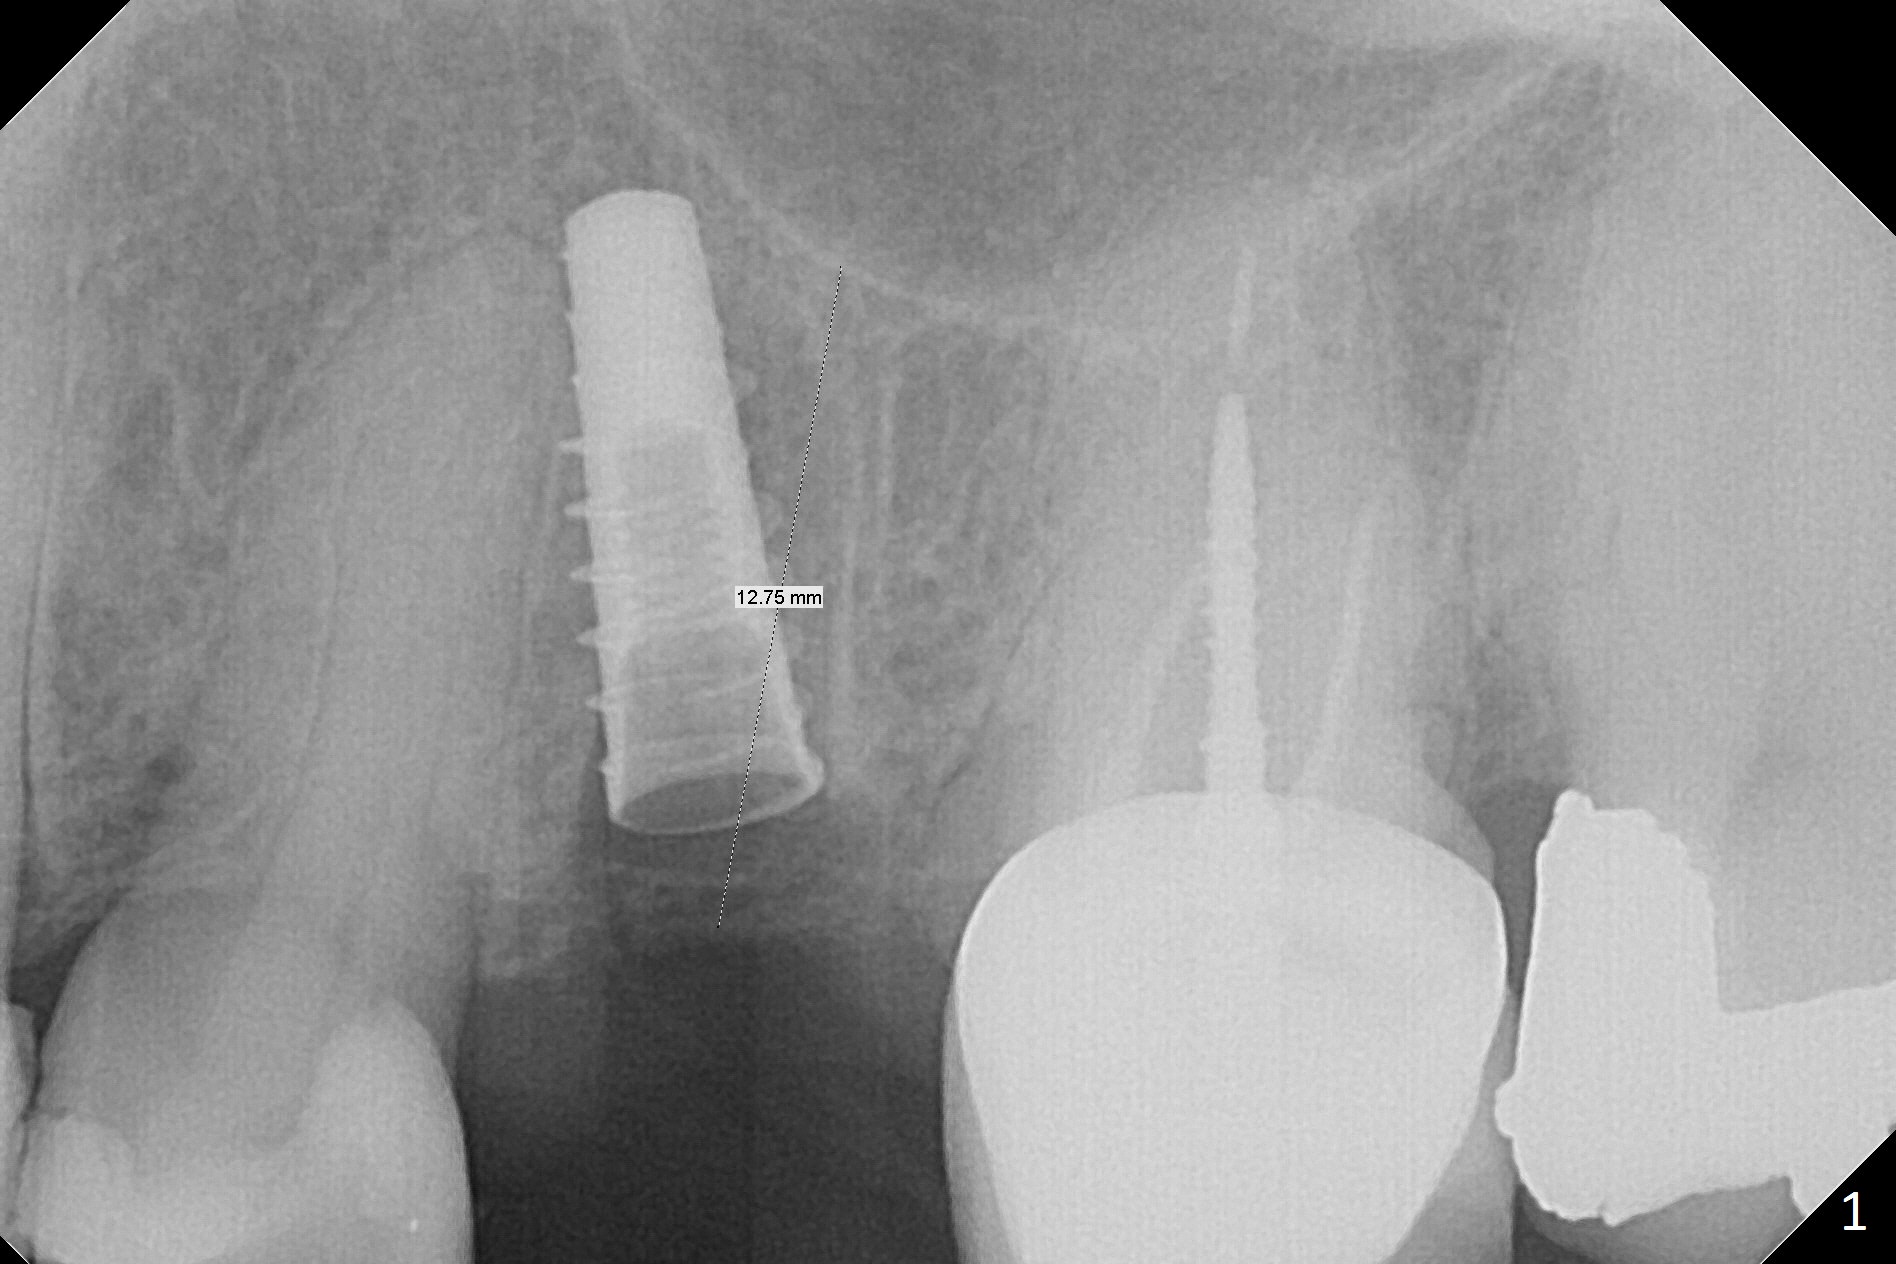

Since the apical native bone is limited at #13 after extraction, no PA is taken until a 4x11 mm dummy implant is placed after 1.6 mm and 3.3 mm drills for 13 mm (Fig.1). After using Lindamann bur to move the osteotomy distal and reusing 3.3 mm drill, the trajectory of a 4.5x11 mm IBS dummy implant improves (Fig.2,3 with low stability). When the implant is removed, the buccal portion of the socket is found to be perforated (Fig.4 P). Although the reason for the perforation is unknown, it is repaired by insertion of a piece of PRF plug, followed by allograft. #1 and 2 in Fig.4 represent the 1st and 2nd osteotomies, as shown in Fig.1 and 2, respectively. The trajectory of the final 5x13 mm implant is acceptable (Fig.5-7, different angulations), so is insertion torque (45 Ncm). After placing a 5.5x4(4) mm abutment, an immediate provisional is fabricated (Fig.8 P) with occlusal clearance (*). The interdental papillae remain in place 12 days postop (Fig.9 *). There is no sign of postop sinus infection. The provisional is loose 18 days postop; the abutment is changed to 5x4(3) mm (Fig.10). It is difficult to catch the mesial margin of the abutment for impression 4 months postop, due to poor oral hygiene and the short cuff (3 mm, Fig.11). The appointment for impression is rescheduled with emphasis on oral hygiene and no wearing the provisional for a few days prior to next appointment. Bone has grown into the space between the 1st and 2nd threads 5 months post cementation (Fig.12) and the bone is normal, solid and dense 2 years 11 months post cementation (Fig.13 >). There is mesial open margin of the tooth #14 (Fig.13,14 *).